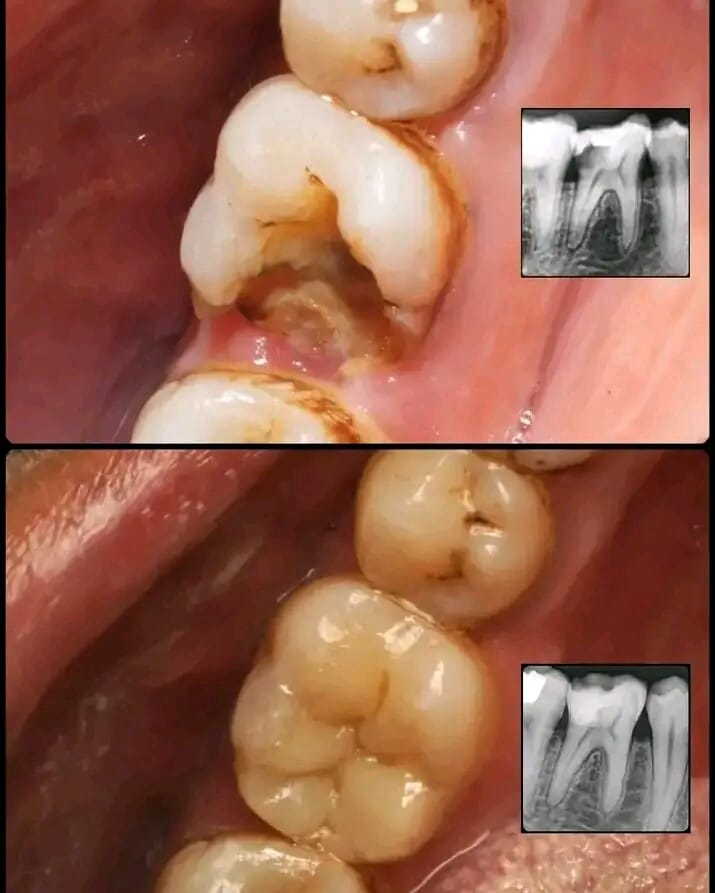

Dental bonding is the most affordable option when it comes to repairing a broken tooth. The dentist will select a composite that matches the color of the patient's teeth and it is applied directly to the broken tooth. The putty-like material is then shaped as desired before being hardened with an ultraviolet light.

Dental Crowns and Bridges

General Dentistry (Check-ups, Cleanings, Fillings)